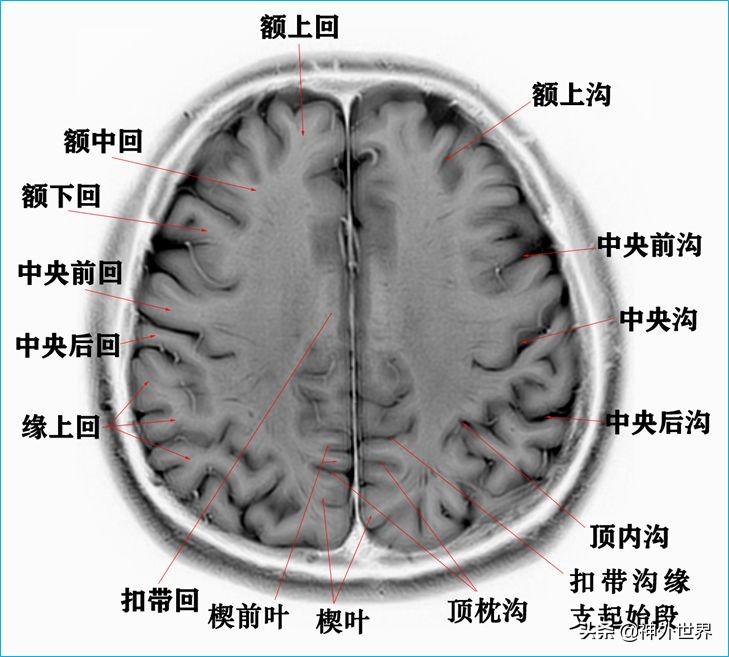

1、水平位连续切片

以下图片均来自我院3.0T核磁共振的T2WI反相图。标注均为我自己完成,水平有限,难免有误,还望各位老师多多指正。谢谢。